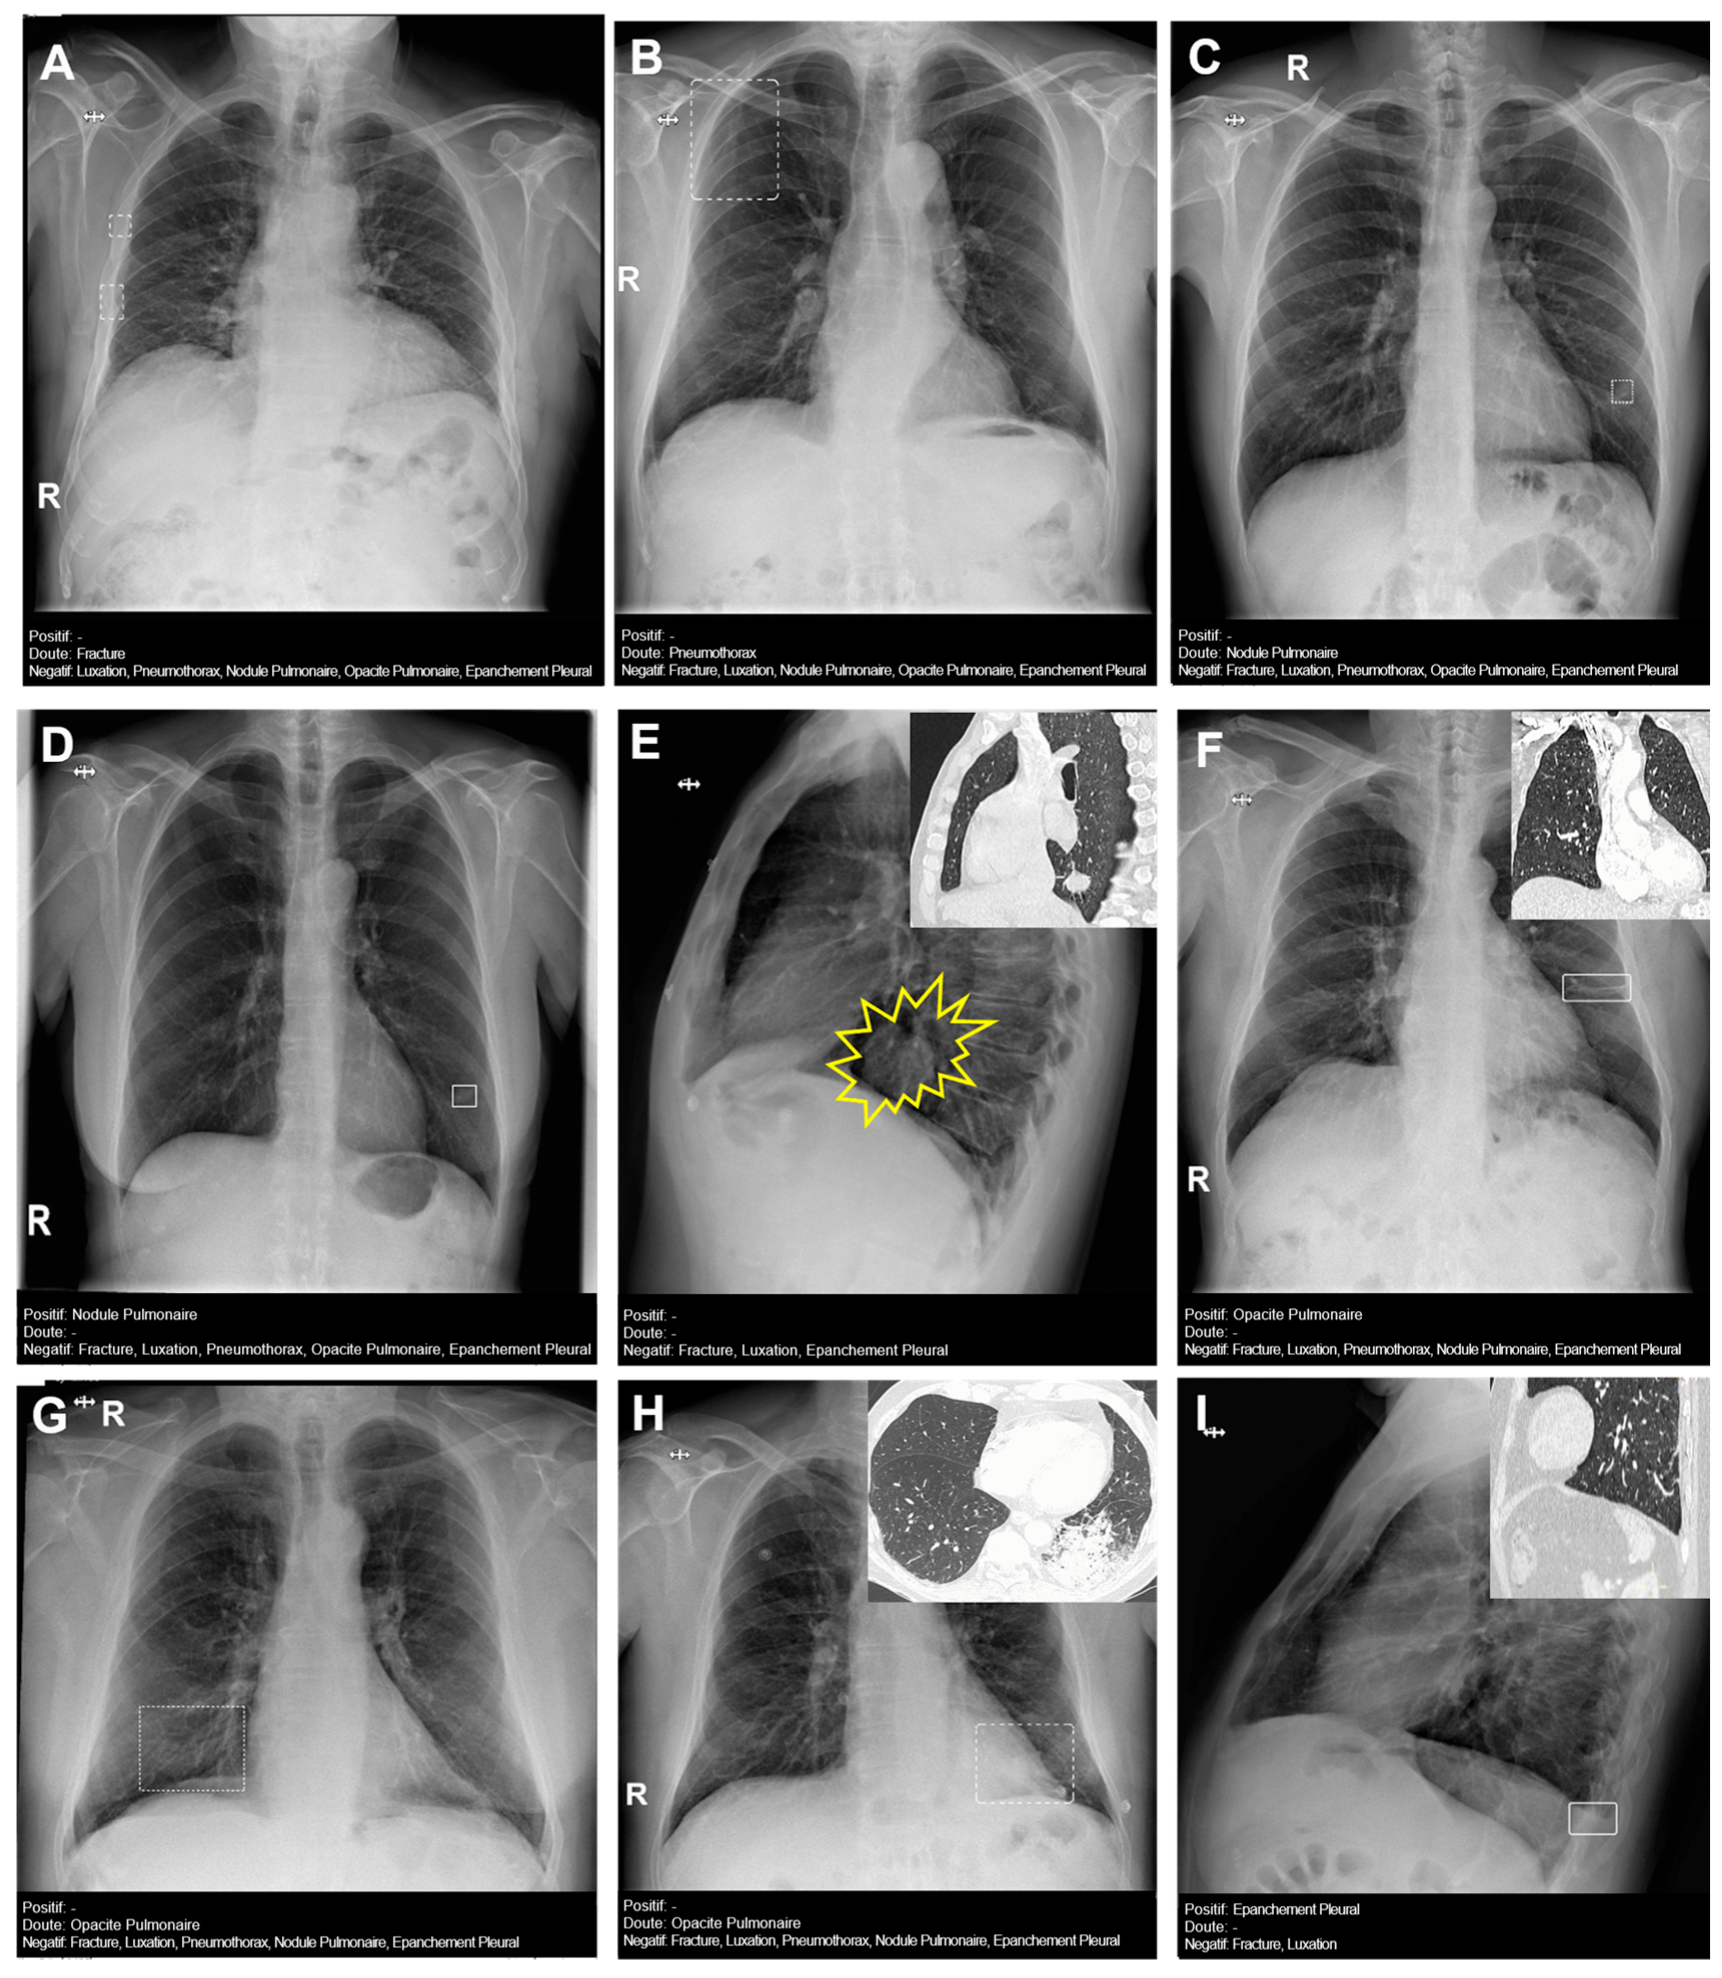

Figure 4 presents several examples of chest radiographs analyzed by the AI.

Figure 4.

Chest radiographs with AI analysis (and E,F,H,I with the associated sagittal (E,I), coronal (F), and axial (H) CT images). (A) False doubtful right fractures outlined with discontinuous boxes (they are chronic). (B) False doubtful right pneumothorax outlined with a discontinuous box. (C) False doubtful left lower lobe nodule outlined with a discontinuous box. (D) False positive left lower lobe nodule outlined with a continuous box. (E) False negative left lower lobe nodule; there is a nodule (outlined in yellow). (F) False positive left pulmonary opacity outlined with a continuous box (it is a laminar atelectasis). (G) False doubtful right lower lobe opacity outlined with a discontinuous box (it is normal pulmonary vascularization). (H) True doubtful left lower lobe opacity outlined with a discontinuous box (retrocardiac infection). (I) False positive pleural effusion outlined with a continuous box (it is a subtle non-pathological erasure of the posterior costophrenic angle).